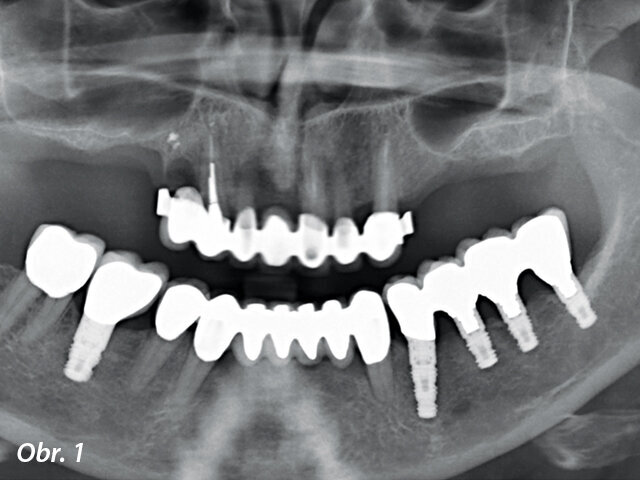

Obrázek 1 zachycuje "split-mouth" případ s oboustranným zákrokem přístrojem INTRALIFT: po oddělení malého krestálního laloku ve tvaru „knížečky“ o rozměru cca 7 × 7 mm bylo dno sinu bezpečně otevřeno pomocí ultrazvukových hrotů Piezotome (obr. 2, 3), membrána sinu oddělená vlivem hydrodynamického kavitačního účinku hrotu Piezotome TKW5 pak byla vtlačena do přístupového kanálu (obr. 4, 5), subantrální konstrukce byla vyplněna 2 cm náhodně přiřazeného biomateriálu a následně byla rána sešita.